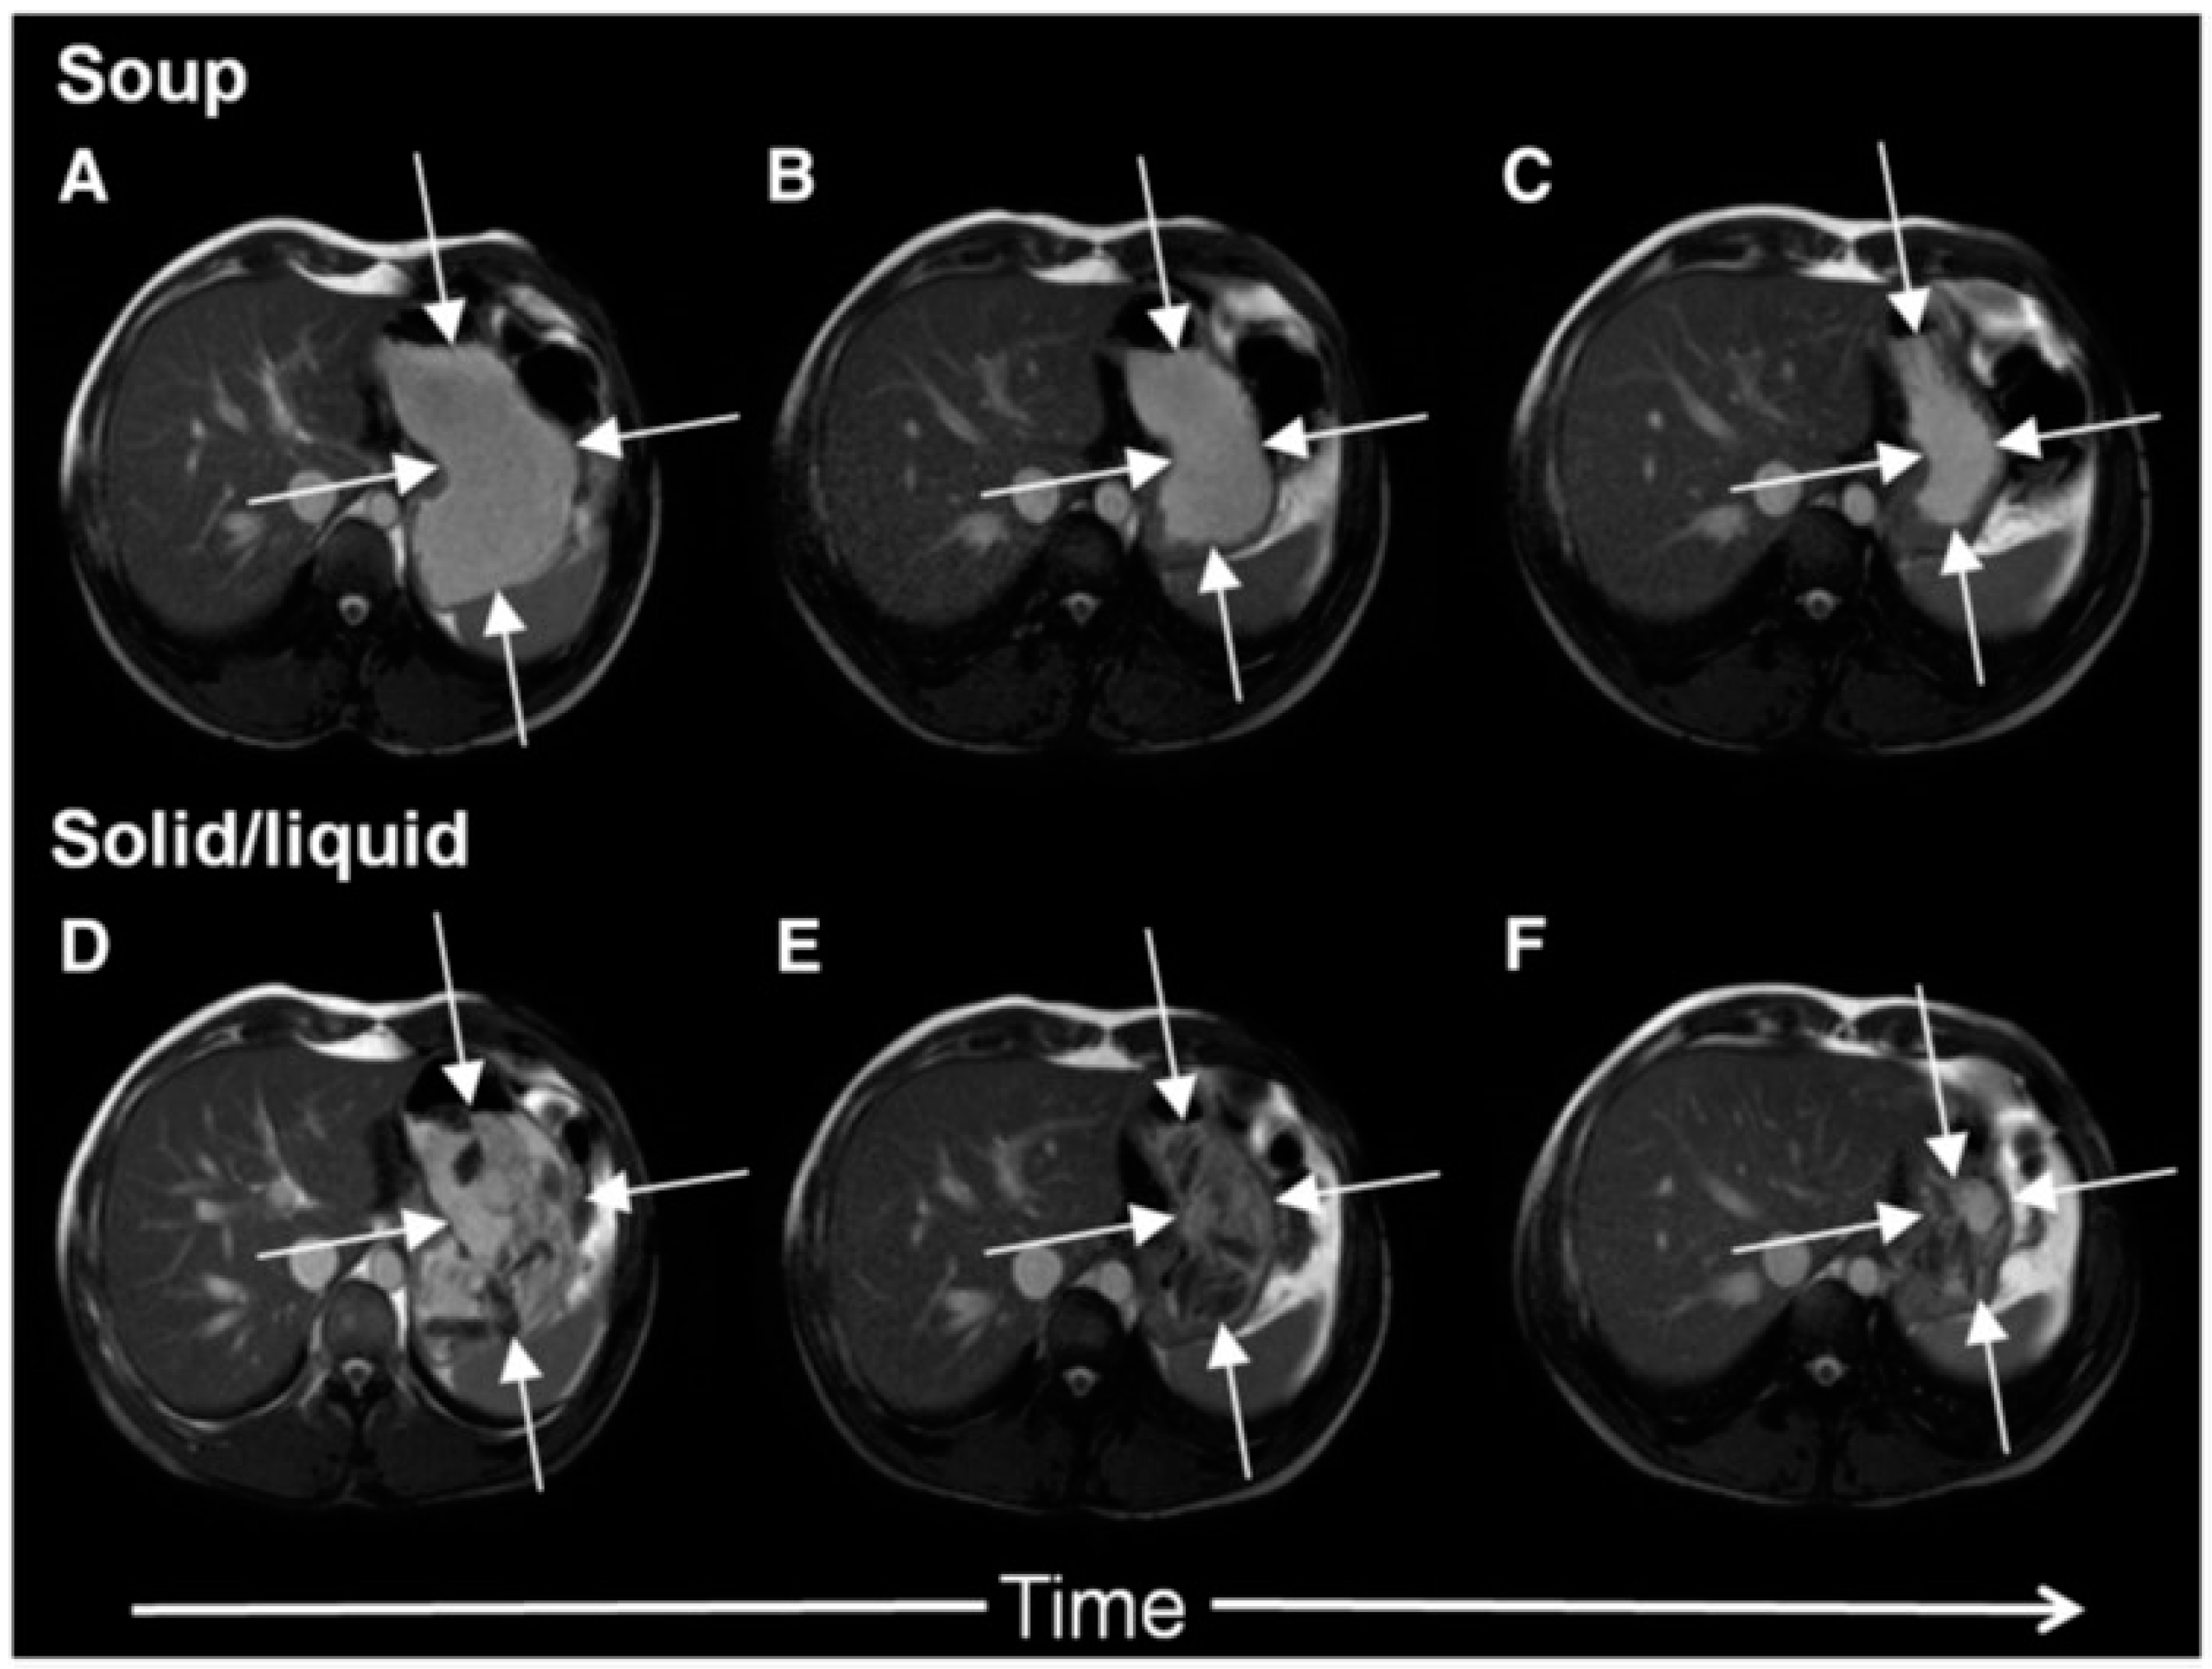

The antral contractions are typically propulsive as they commence in the mid stomach but as they approach the pylorus change to a more systolic pattern with pyloric closure occurring before all the chyme is expelled into the duodenum. This effectively restricts gastric emptying to particles <2 mm in diameter and creates shearing forces as the remaining material is forced backwards away from the contracting pylorus. The resulting forward and backward flows can be detected using flow sensitive MRI sequences as mentioned previously. The net effect is the earlier emptying of the fluid component of mixed liquid/solid meals, which make up most of what normal humans ingest. MRI images can clearly show the heterogeneity of food immediately after food ingestion, which varies according to the meal type (Figure 1). A rice pudding meal typically separates into an uppermost fluid layer above a dependent solid component, whereas a roast chicken and vegetable meal produces a very heterogeneous intragastric distribution of solid and liquid. Other more homogenous meals like porridge, soup or bread produce a uniform intra-gastric mass from which no separation of the liquid and solid phase is possible. When we compared an equicaloric rice meal with wholemeal bread, we found that while the rice pudding meal separated into a solid and liquid phase, the wholemeal bread formed a rather homogeneous mass with no clear separation of fluid and solid. While the rice meal allowed the stomach to sieve the meal and empty the fluid faster than the solid, sieving was not possible with the more homogeneous bread meal and as a consequence the gastric volume fell more slowly. In contrast, once the wheat entered the small intestine it was rapidly absorbed and the small bowel water content (SBWC) was consistently lower than after the rice meal postprandially, suggesting than any sensation of bloating after a bread meal most probably comes from gastric distension [4]. Other groups have also used MRI to document gastric sieving and its prevention by homogenization with both solid [6] and liquid [7] meals.

In Figure 2 it is shown how a typical solid meal taken with water drink (D–E) fills the stomach with heterogeneous content from which the fluid can be preferentially emptied causing a faster fall in total gastric volume and hence feeling of fullness. We compared this with the same meal blenderised to create a homogeneous soup (images A–C) and showed that the volume of the stomach fell more slowly with the soup and this was associated with more prolonged satiety [5].

Figure 1. Gastric MRI images of different mixed solid/liquid meals: (A) Soup, (B) roasted chicken and vegetables, (C) whole wheat bread and (D) rice pudding. Reproduced from [4], Springer Nature 2013, under Creative Commons CC-BY license and from [5], Oxford University Press 2012, with permission.

Figure 2. Cross-sectional MRI images showing a stomach at 0, 60 and 120 min after ingesting either roast chicken and vegetables (panels D, E and F respectively) or the same meal blenderised to create a homogeneous soup (panels A, B and C respectively). The solid meal taken with water appears heterogeneous, fluid can be preferentially emptied reducing gastric volume and hence the feeling of fullness. The same meal when blenderised appears homogeneous, gastric volumes fall more slowly with time which is associated with more prolonged satiety. Reproduced from [5], Oxford University Press 2012, with permission.